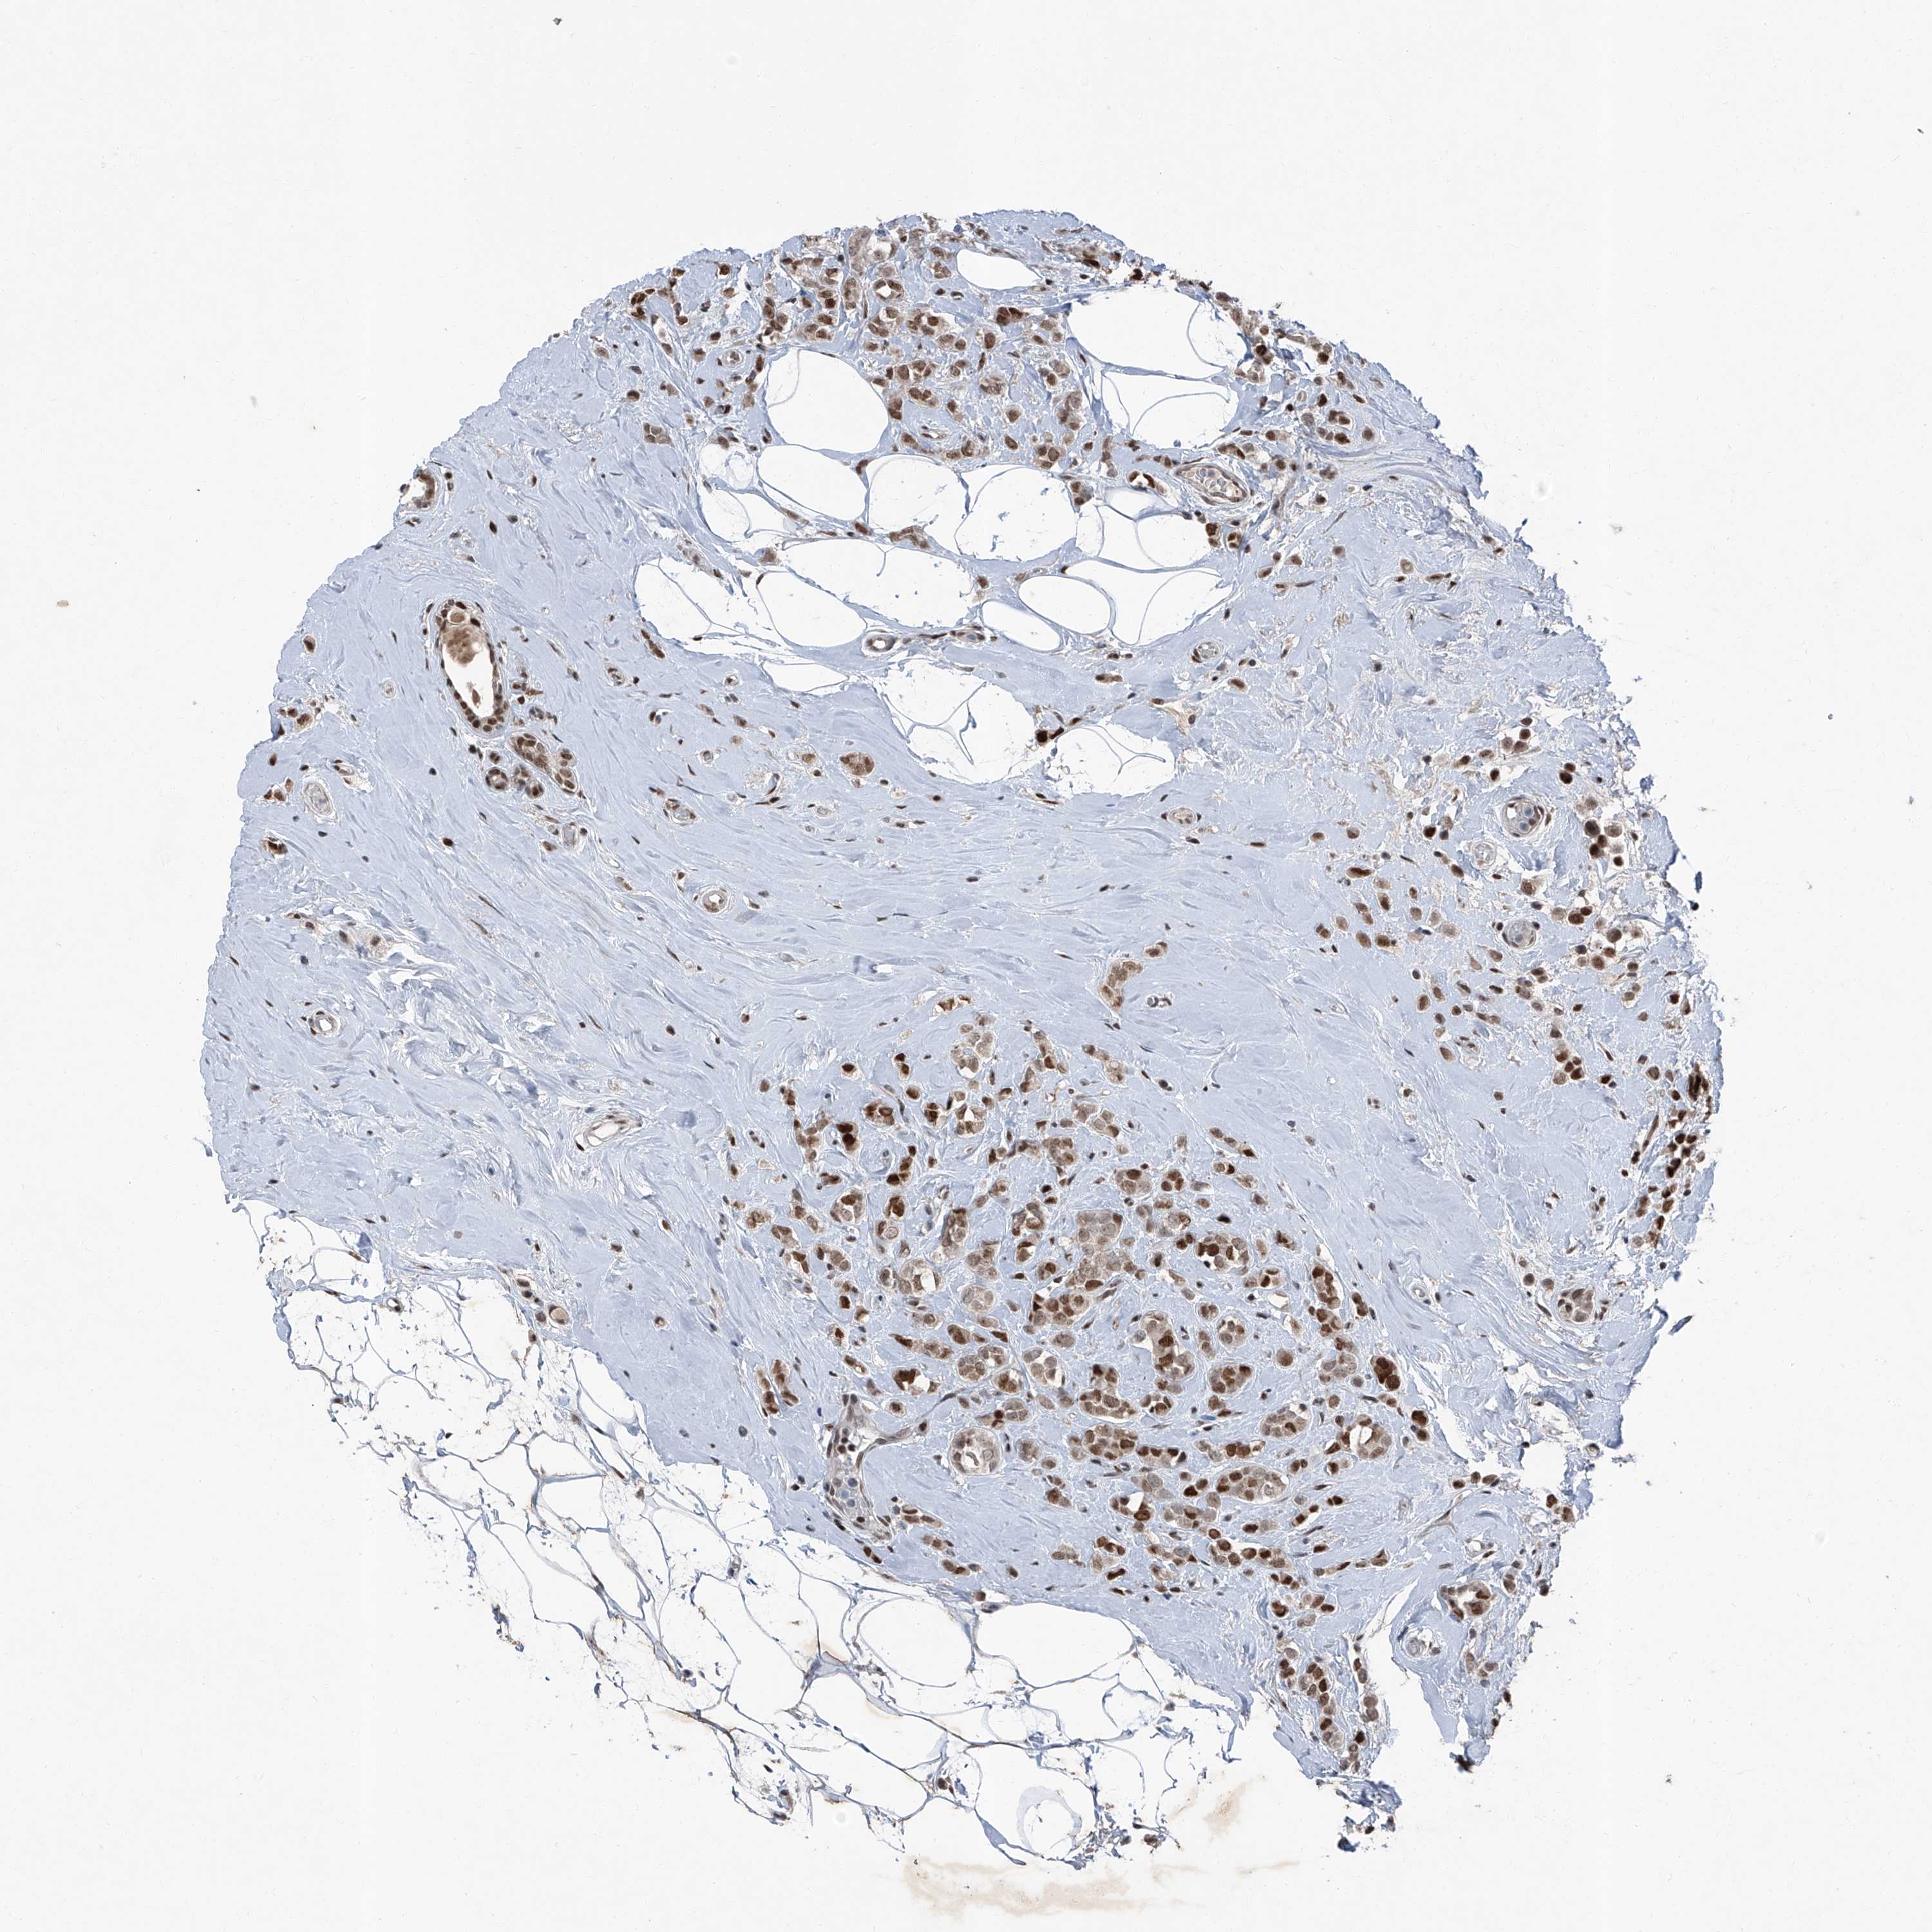

BRCA TCGA BRCA VALIDATION PROTEIN EXPRESSION

ANTIBODIES

AND

VALIDATION